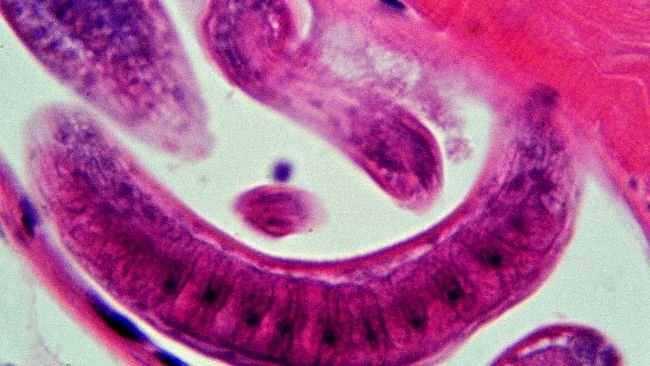

A Junta de Castela e Leão confirmou um foco de triquinose

A Junta confirma um foco de triquinose que afecta 16 pessoas na Província de Leão

O novo regulamento altera alguns aspectos do controlo de parasitas em relação à desmancha e métodos analíticos alternativos.

O novo Regulamento modifica o relativo à amostragem, método de referência para detecção e condições de importação relativamente ao controlo das triquinas.